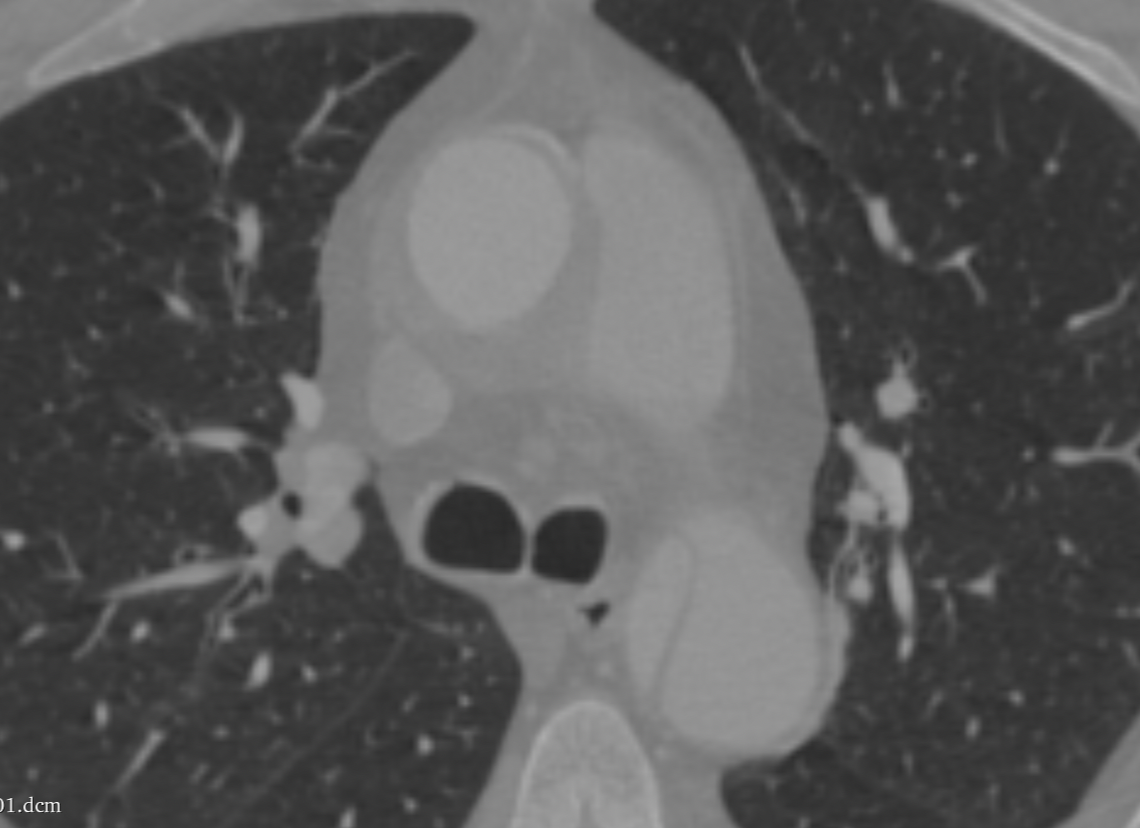

Welcome to our comprehensive cardiology annotation services. Our team of experienced medical professionals and advanced technology combine to provide accurate and detailed annotations for cardiology imaging data. From EKGs to echocardiograms, we offer precise and reliable annotations to support research, diagnosis, and treatment planning. Whether you're in need of precise measurements, feature detection, or anomaly identification, our services are tailored to meet your specific needs. Trust us to deliver high-quality, efficient, and insightful annotations for your cardiology data.